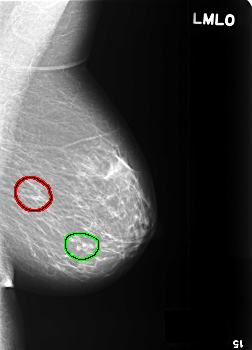

FILE: C_0361_1.LEFT_MLO.OVERLAY

TOTAL_ABNORMALITIES 2

ABNORMALITY 1

LESION_TYPE CALCIFICATION TYPE PLEOMORPHIC DISTRIBUTION CLUSTERED

ASSESSMENT 4

SUBTLETY 3

PATHOLOGY MALIGNANT

TOTAL_OUTLINES 1

BOUNDARY

ABNORMALITY 2

LESION_TYPE CALCIFICATION TYPE EGGSHELL DISTRIBUTION SEGMENTAL

ASSESSMENT 2

SUBTLETY 5

PATHOLOGY BENIGN_WITHOUT_CALLBACK